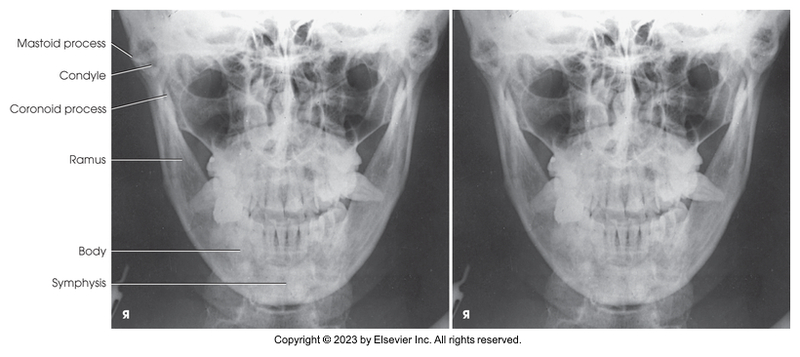

PA projection of mandibular rami

PA axial of mandibular rami

PA projection of mandibular body

PA of mandibular rami

PA axial of mandibular rami

PA of mandibular body